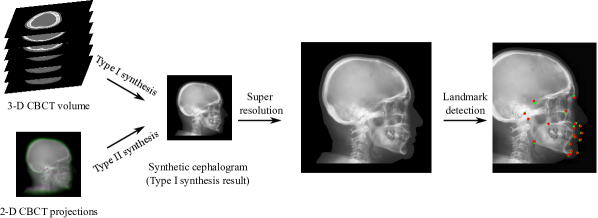

Refer to caption

Fig. 1: A graphical abstract of our contributions to cephalometric analysis in dental CBCT systems.

In order to address the above mentioned aspects in cephalometric analysis, the following contributions, displayed in Fig. 1 as an overview, are made in this work:

1. Image contrast: a nonlinear sigmoid-based intensity transform according to the optical property of X-ray films is proposed for Type I cephalogram synthesis;

2. Low dose: direct cephalogram synthesis from dual CBCT projections is proposed, where the advantage of using dual projections over one projection, the selection of patches, and the feasibility of one model for multi-quadrant patches are elaborated;

3. Image resolution: super resolution (SR) techniques using different adversarial generative networks (GANs) are investigated;

4. Landmark detection: an efficient automatic landmark detection method is proposed, which is applicable to real and synthetic cephalograms.